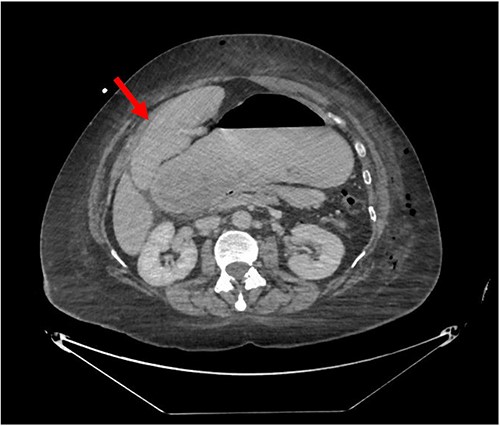

Despite the insertion of the NGT yielding 1500 cc output in 24 hours, the patient continued to experience severe abdominal pain. Urgent abdominal and pelvic computed tomography (CT) scans were taken, as seen in Figs 2–4. The CT scans showed gastric distension and the spleen positioned anteriorly in the right upper quadrant. Consequently, the decision was made to promptly bring the patient to the operating room for a diagnostic laparoscopy with plan to detorse the spleen.

CT of the abdomen and pelvis (sagittal slice) showing gastric distention and the spleen positioned anteriorly.

CT of the abdomen and pelvis (axial slice) showing gastric distention and the spleen positioned anteriorly in the right upper quadrant.

CT of the abdomen and pelvis (coronal slice) showing gastric distention and the spleen positioned in the right upper quadrant.

Our patient’s pre-existing conditions presented challenges in distinguishing between expected postoperative discomfort and potential complications following her recent adrenalectomy. This uncertainty, combined with a normal WBC count, absence of fever, and regular bowel function, initially led the medical team to attribute her pain to the recent surgery two days prior, delaying her diagnosis and potentially exacerbating her condition. Subsequent imaging became imperative, revealing a persistent large gastric bubble despite NGT decompression, and malposition of the spleen (Fig. 3). This prompted immediate preoperative measures to facilitate a diagnostic laparoscopy.